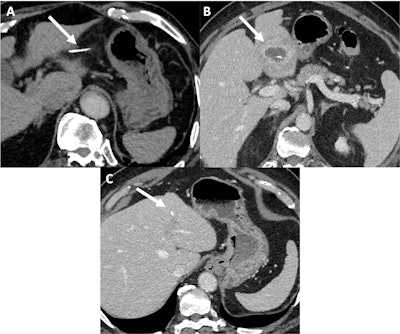

A 74-year-old man underwent a contrast-enhanced CT for colonic adenocarcinoma extension assessment (A). A fishbone was found, which was located purely into the omental bursa. There was no sign of gastric perforation (no pneumoperitoneum and no gastric abnormality) but there was discrete fat stranding around the fishbone with no collection (the patient was asymptomatic). Two and a half months later the patient presented with significant change in his general condition with an inflammatory syndrome alongside nausea. He presented to the emergency department and a contrast-enhanced CT was performed (B). In the portal venous phase, the fishbone had migrated into the left liver lobe forming an abscess of 5 cm (maximal diameter). The patient had a C-reactive protein (CRP) level of 164 mg/l and a WBC of 14 G/L. The patient received antibiotic treatment and percutaneous drainage. On follow up imaging (C), 10 months later, the remaining fishbone was present but the liver abscess has completely disappeared.Ben Zitoun et al; EJR